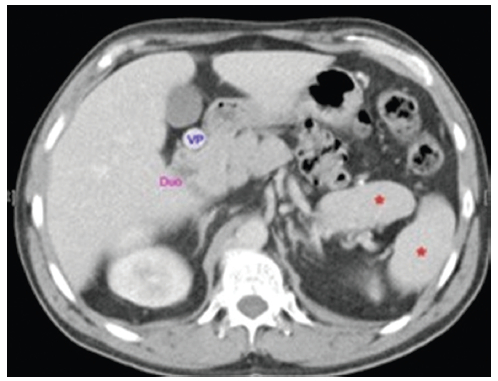

Otras anomalías que se pueden encontrar son la vena porta preduodenal, que puede interferir en el desarrollo normal del páncreas, como en el caso 4 (Fig. 10) (2.

Páncreas

Las anomalías del páncreas son frecuentes y bien conocidas. El hallazgo más frecuente es el de un páncreas trunco, con presencia de la cabeza pancreática y una pequeña parte del cuerpo como se vio en los casos 1, 3 y 4 (Fig. 11). Las anomalías del páncreas y bazo se asocian, debido al desarrollo embrionario común14.

Bazo

La mayoría de los casos de síndrome de heterotaxia con isomerismo izquierdo se asocia a la existencia de múltiples bazos, de distinto tamaño pudiéndose encontrar en cualquier localización, pero más frecuentemente próximos a la curvatura mayor del estómago, como en los casos 1, 3 y 4 (Figs. 11 y 13). Esta estrecha relación está determinada por el desarrollo embriológico14.